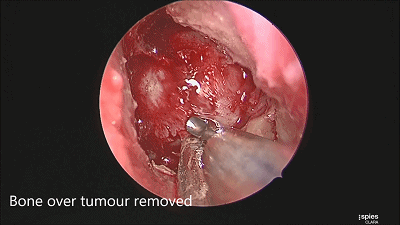

▼用磨钻从鞍底下部磨开鞍底骨质。

▼根据肿瘤大小,用万向椎板咬骨钳开放直径约1-1.5cm的骨窗,显露鞍底硬膜。

▼尖刀“X”划开鞍底硬膜